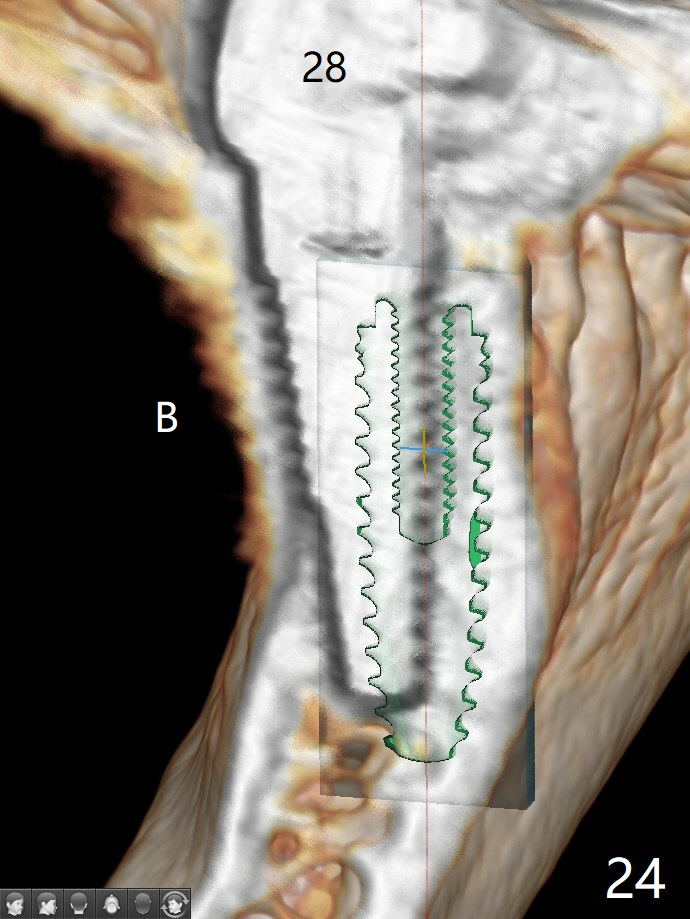

Two of 2.5 mm 1-Piece Implants M

The edentulous ridge at #30 is narrow (Fig.1). After ridge reduction, osteotomy is initiated with 1.2 mm drill for 10 mm; the mesial osteotomy is to be changed (Fig.2 red line). Using a 1.2 mm drill placed in the distal osteotomy (Fig.3 D), the mesial osteotomy changes in trajectory with subsequent placement of a 2.5x10(4) mm 1-piece implant. Since the mesial implant is high in occlusion, the cuff of the distal implant is changed to be 2 mm (Fig.4 (shorter black line)). Panoramic X-ray is taken to show no violation of the Inferior Alveolar Canal (Fig.5 red dashed line). These two 1-piece implants are slightly lingually placed (Fig.6). The crestal bone around the implants resorbs without thread exposure 5 months postop (Fig.7). Impression is taken for a splinted crown (Fig.8-12). There is no metal show around the 2.5 mm 1-piece implants 6 months postop (advantage) vs. that at #28 and 29 (Fig.13). Bitewing is taken post cementation to determine whether residual cement is present (Fig.14). There is periodic swelling and pain in the lower right quadrant 2 years post cementation (Fig.15). In fact periimplantitis appears to have developed at #28 (Fig.16) with loss of the buccal bone (Fig.17,18). The buccal bone loss is less at #29 (Fig.19) and #20 (Fig.23) and no at #30 mesial and distal implants (Fig.20,21). A much smaller implant will be placed lingually at #28 immediate (Fig.24,25).